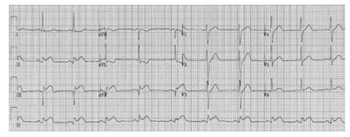

Um paciente de 62 anos de idade, previamente hipertenso,

apresentava dor torácica típica já há 2 horas, irradiando para

o braço esquerdo, associada à sudorese e às náuseas. No

exame físico, apresentava-se estável hemodinamicamente.

O eletrocardiograma de admissão está disposto logo a

seguir. O paciente chegou ao serviço médico às 19 horas,

na troca de plantão, passando-se, assim, 45 minutos sem

reavaliação. O paciente estava em um hospital sem serviço

de hemodinâmica, e o centro de referência mais próximo

tinha um tempo estimado de recebimento do paciente em

80 minutos.

Com base nesse caso clínico hipotético, assinale a opção que apresenta a conduta adequada.